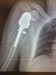

električky pri nastupovaní. Mam som rozbitú hlavu , male krvácanie do mozgu a zlomené rameno . Prvu pomoc mi poskytol vodič električky , keďže prehadzoval vyhybku a všetko videl. Úrazovka ma previezla do

nemocnice Mickiewiczova , kde som bol 10 dni , neskou mi rameno operovali v Ružinove 18.12.2020.